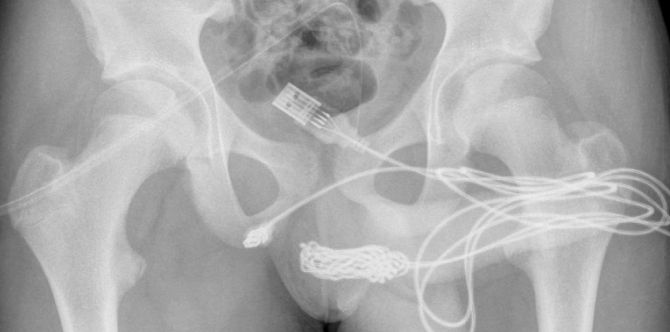

Image courtesy: University College Hospital London

X-rays revealed that there was a huge knot of USB cable inside the teenager, and surgeons managed to remove it by making an incision in the region between his genitals and anus.

The report said: “Both ends of the wire were pulled out successfully through the external urethral meatus (opening of the urethra)”.